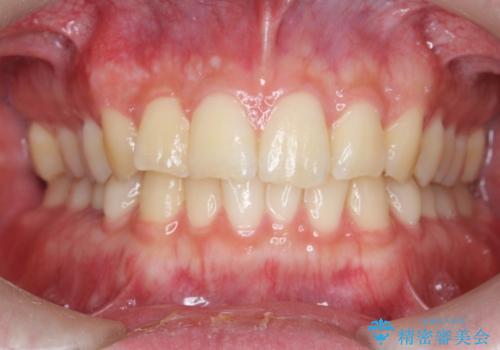

[ 前歯のねじれ・がたつき ] マウスピース矯正

![[ 前歯のねじれ・がたつき ] マウスピース矯正の症例 治療前](https://seimitsushinbi.jp/wp/wp-content/uploads/2024/02/4007c6479f6bce11863dcdd32ed5e39b-500x350.jpg?v=1708502552)

![[ 前歯のねじれ・がたつき ] マウスピース矯正の症例 治療後](https://seimitsushinbi.jp/wp/wp-content/uploads/2024/02/e7a01485e4f4dd0da04705fde4cc34cc-500x350.jpg?v=1708502585)

インビザライン モニター治療 前歯のねじれをまっすぐに